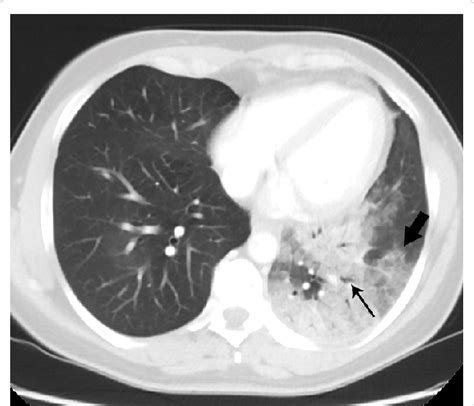

Discover what a node in lung CT scan findings means. Learn about pulmonary nodules, the difference between benign and malignant growths, and why follow-up imaging is essential for lung health. Understand diagnostic procedures, risk factors, and when to consult a specialist for a comprehensive lung nodule assessment to ensure early detection and peace of mind.

Read full article: Node In Lung Ct Scan